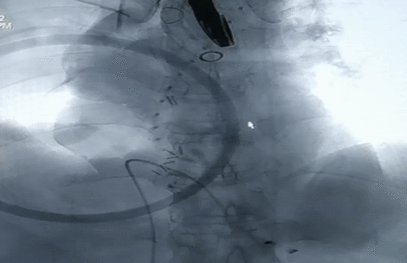

升主动脉准备:

瓣膜释放完成